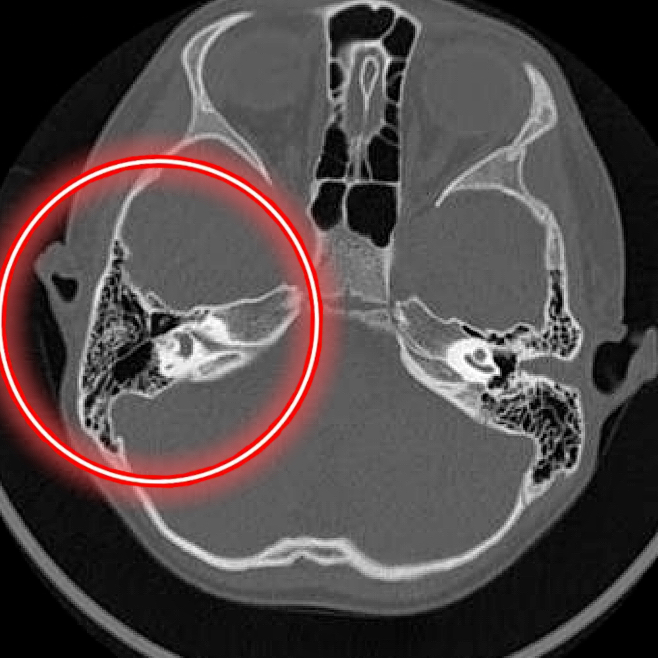

影像学检查—CT

左侧外耳廓较右侧偏小,外耳道骨性闭锁,听小骨发育不良。右侧外耳道狭窄伴随膜性闭锁。